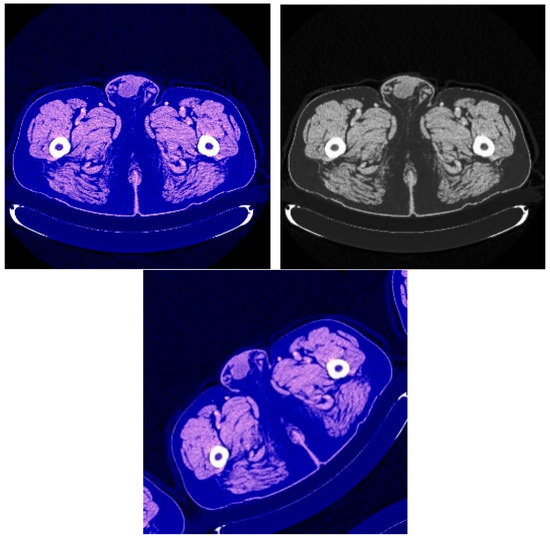

This process was repeated for all training phases, and in phases 18 and above, it was noticed that this accuracy did not improve more than a certain threshold, meaning that every time the model was trained on a set of images from the training sample, it checked images in the validation sample and obtained a certain accuracy. In this case, the accuracy reached 0.991, meaning that the accuracy of the model during the training and validation phases was 99.1%. The visual examples of the results of the model for detecting liver cancer from the dataset are shown in Figure 9.

Figure 9.

The visual results of the second model for cancer detection on LiTS dataset: (a) normal case (no tumor detection); (b) abnormal case (tumor detection).

From the previous results mentioned in Section 3, it was observed that the first proposed method (the combination of DeeplapV3 and ResNet 50) achieved better accuracies than the second method (the combination of VGG-16, ResNet 50 V2, U-Net and LSTM) using both datasets. Therefore, we confirmed the first method to be our method. We also observed from the results that the first method obtained a high accuracy of 99.5% on small data (the case of the second dataset), which makes it more robust and efficient than other previous deep learning methods. In addition, when using the first dataset, as shown in Figure 7, it was observed that the first model could accurately detect cancer from the normal image. However, we can see from Figure 9 that the second model made some noise when detecting cancer from a normal image (as shown in Figure 9a). In terms of the second dataset (small data), we can observe from Figure 12 and Figure 16 that, when detecting cancer from the image, the two models detected cancer with some noise, but the first model was still better than the second model, with less noise. We employed the ReLU activation function in our models because it does not become active in all neurons at the same time. In addition, ReLU gives the highest accuracy, compared with other nonlinear activation functions, such as the Tanh activation function. Table 5 shows a performance comparison when using ReLU as an activation function and other nonlinear activation functions on the 3D-IRCADb-01 dataset.